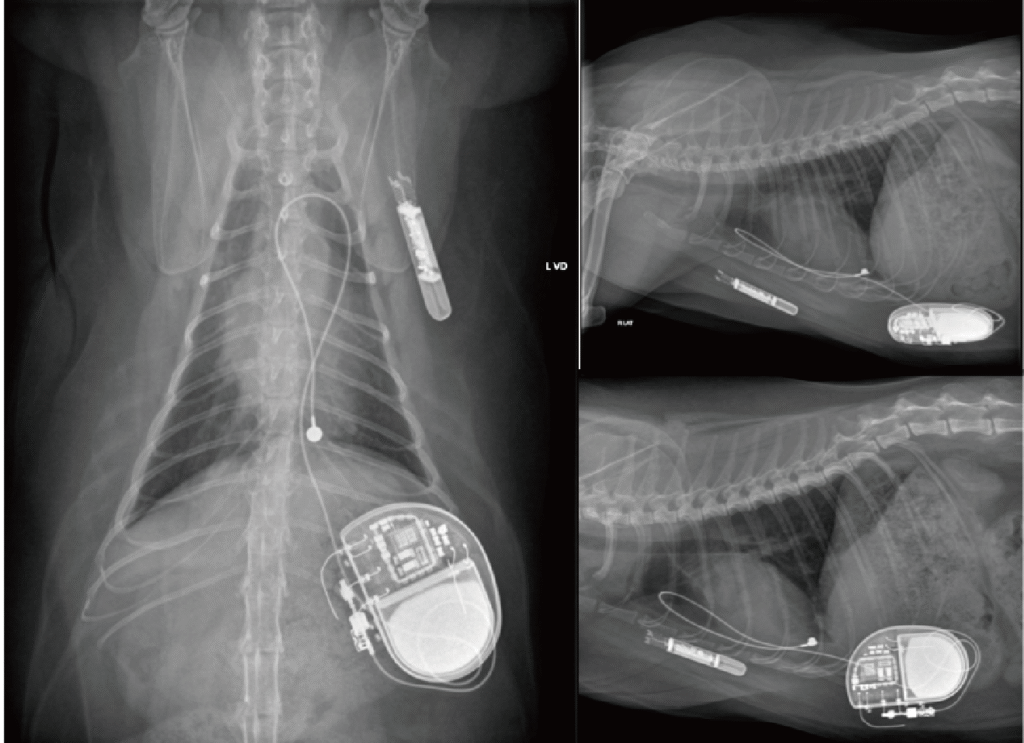

2025/1/7 植入 Medtronic Reveal LINQ™(圖 2);1/8 起 ICM 陸續自動記錄到第二級與三級 AV block 交替,無超過 3 秒的停搏(pause)且無臨床症狀;期間 24 小時平均心率多在 125–158 bpm,最高可達 333 bpm。於 2025/1/15 記錄到一長達10秒的高度AV block,但家屬未觀察到症狀(圖 3)。約 3 月中,心率轉為永久性三級 AV block,整日平均心率下降至 70–75 bpm,家屬未觀察到任何臨床症狀。由於整日平均心率逐漸下降至60-65 bpm,雖無臨床症狀,於5/1 起家屬同意投予 theophylline 9.124 mg/kg PO q12h 與 cilostazol 9.884 mg/kg PO q12h,24 小時平均心率於服藥後一度回升至 80–90 bpm,惟約一個月後逐漸回落;6 月起即使持續服藥,平均心率僅 60–65 bpm。8/9 15:03 家屬觀察到叫聲後癱軟,ICM 同步紀錄大於 5 秒心搏停止(圖 4);8/10 回院評估後建議置入人工節律器,並於同日檢測 theophylline濃度 18.9 μg/mL,顯示已無進一步調高劑量的空間。8/26 經腹腔橫膈膜通道放置單腔心外膜節律器(VVIR)(圖 5);植入時檢測內在心率僅 50 bpm。術後門診檢查顯示 >99% 依賴節律器驅動,臨床症狀消失,活動量與睡眠品質顯著改善。